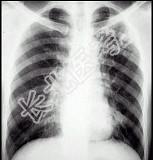

- 单项选择题男性,18岁, 发热1个月,体温37.5~38.5℃, 抗感染治疗无好转,消瘦明显, 胸片见图,最可能的诊断是 ( )

A、肺门淋巴结核

B、淋巴瘤

C、结节病

D、肺癌,淋巴结转移

E、原发性肺结核